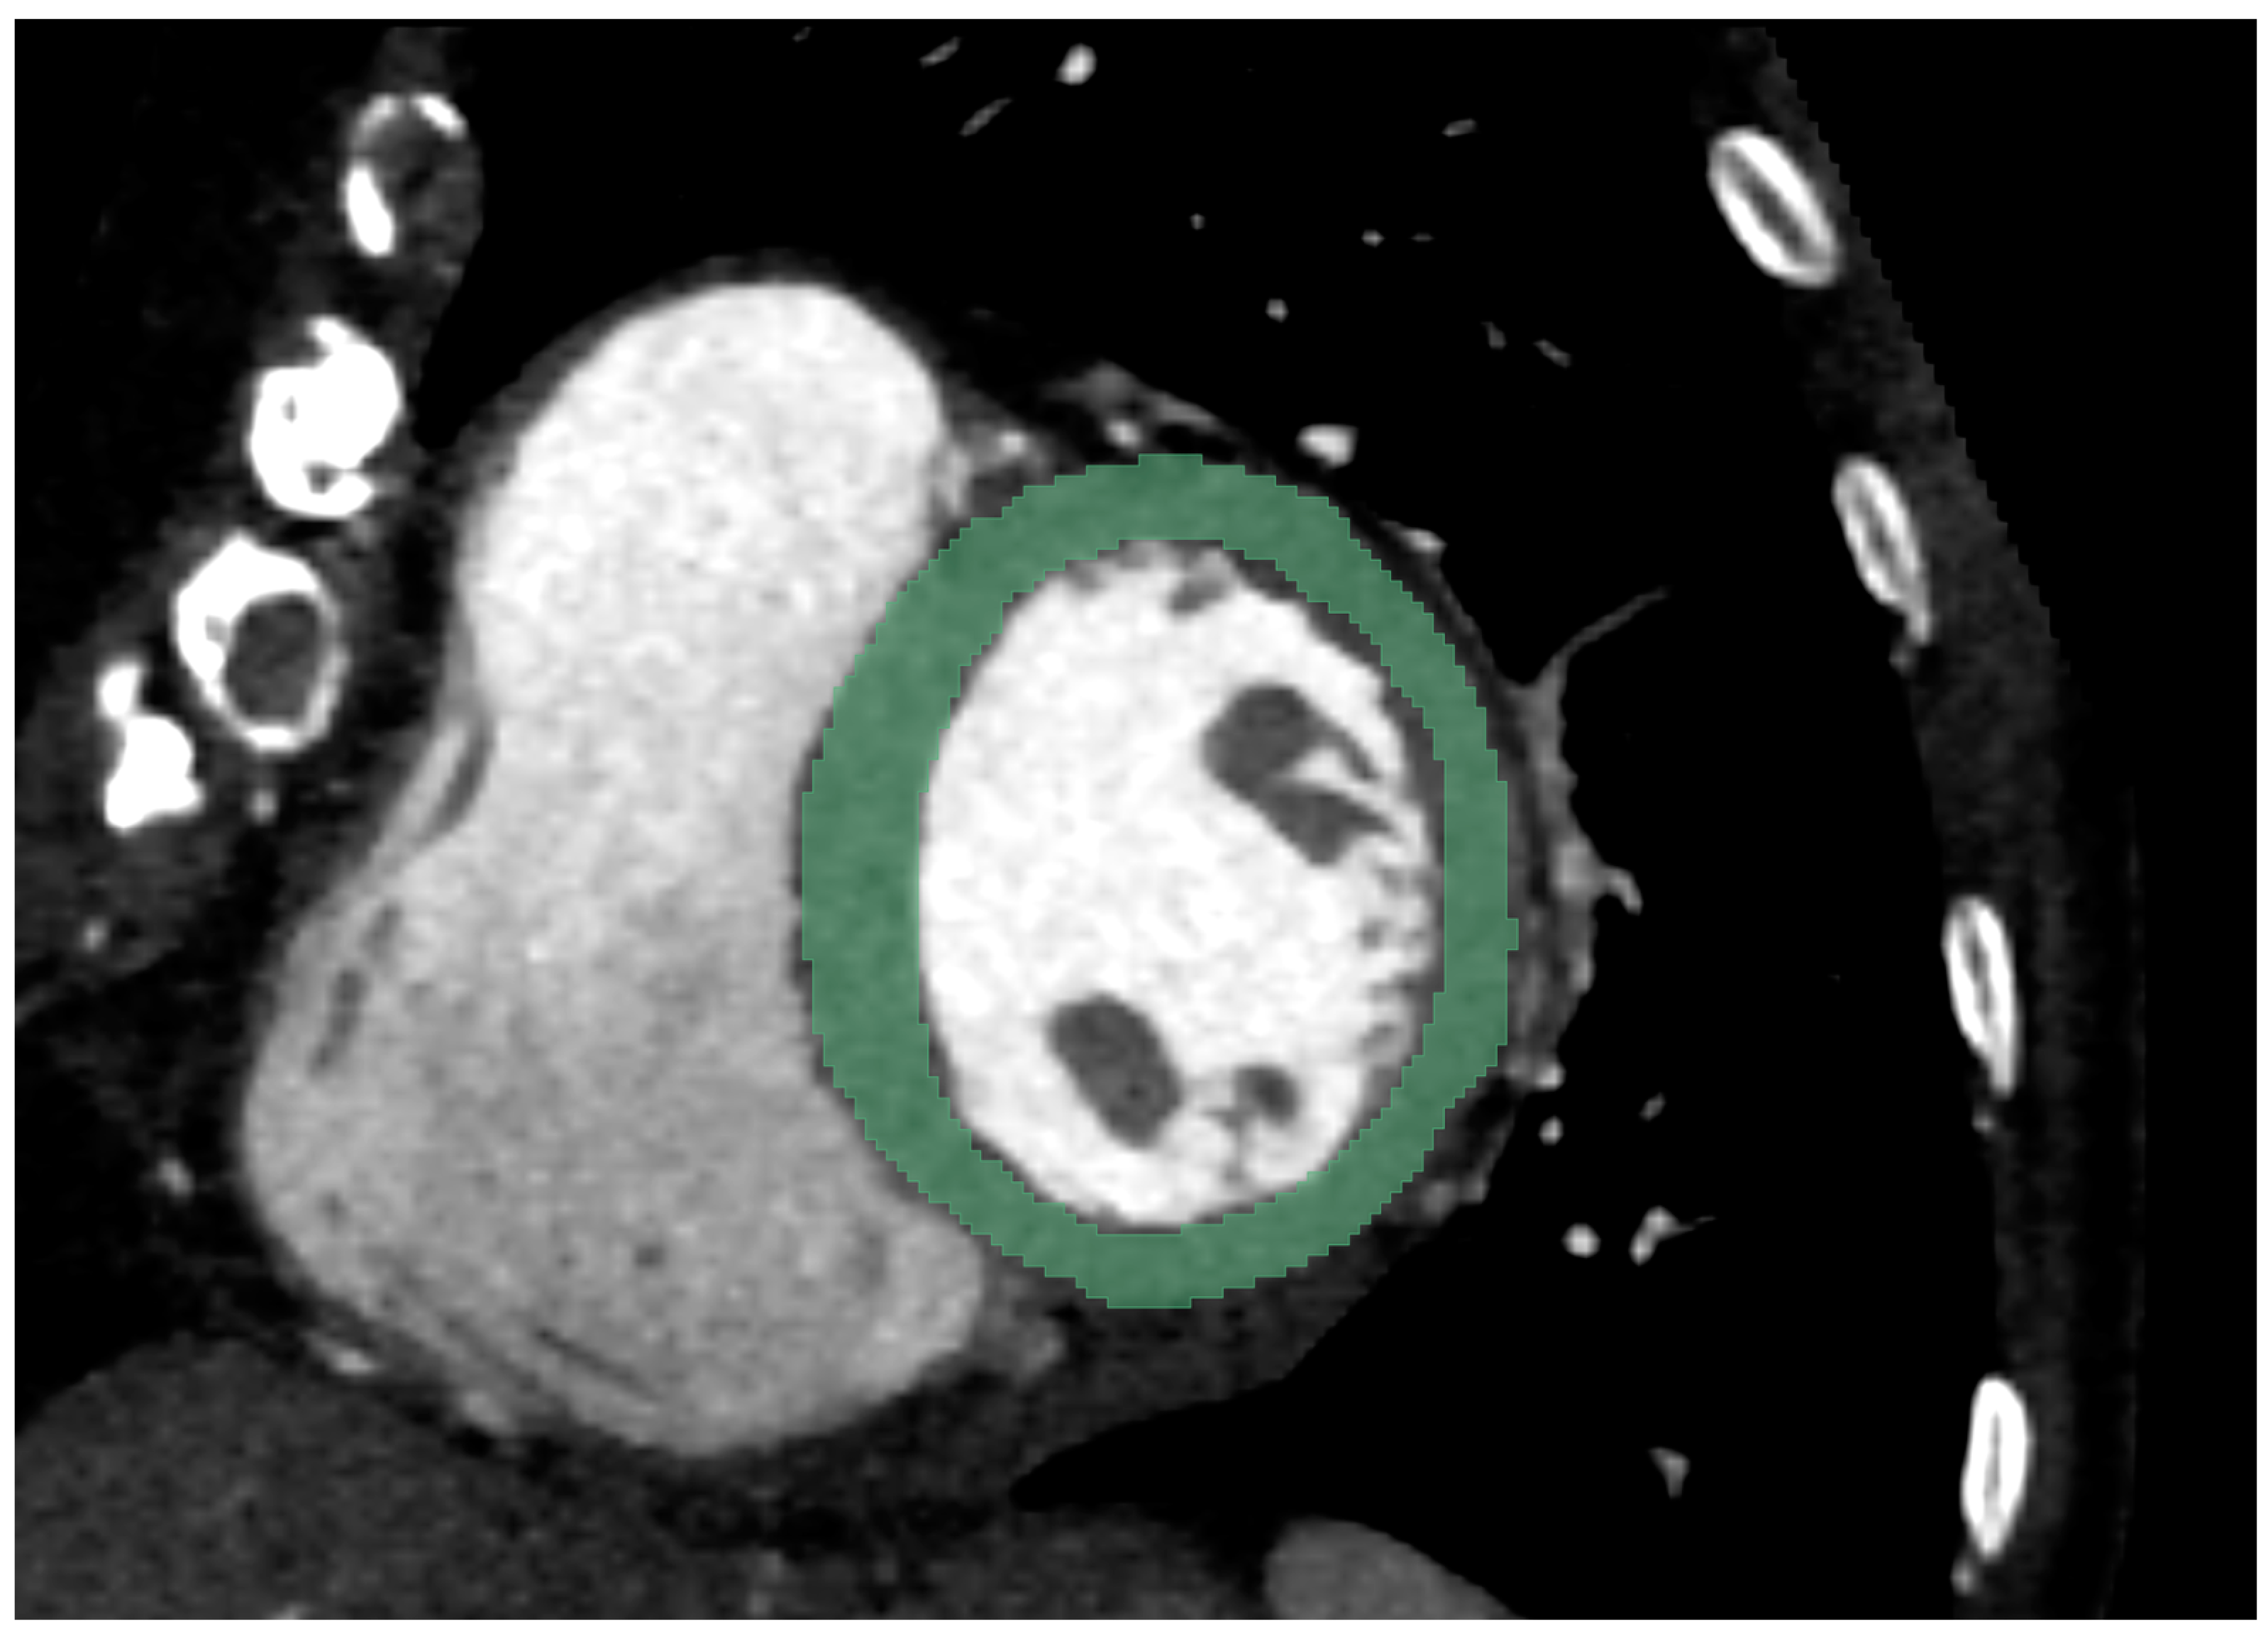

2.2. Chest CT Imaging Analysis

2.3. Radiomics Feature Extraction